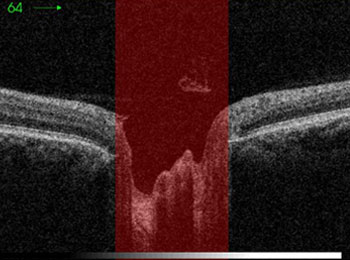

Qu’est-ce que le glaucome ?

Le glaucome est une maladie dégénérative du nerf optique, entraînant une perte graduelle de la vision, commençant généralement en périphérie et progressant vers le centre. S'il n'est pas traité, le glaucome peut conduire jusqu'à la cécité.

Généralement, le glaucome survient en raison d'une évacuation insuffisante du liquide à l'intérieur de l'œil provoquant une augmentation de la pression intraoculaire, ou d'un moins bon apport sanguin vers le nerf optique. Il est difficile de déterminer les causes de son apparition, même si certains facteurs favorisants et prédispositions sont connus : l'hérédité, une blessure à l'œil, d'autres problèmes oculaires (myopie, cataracte, uvéite prononcée…) ou certaines maladies (hypertension, diabète, hyperthyroïdie, troubles cardiovasculaires…)